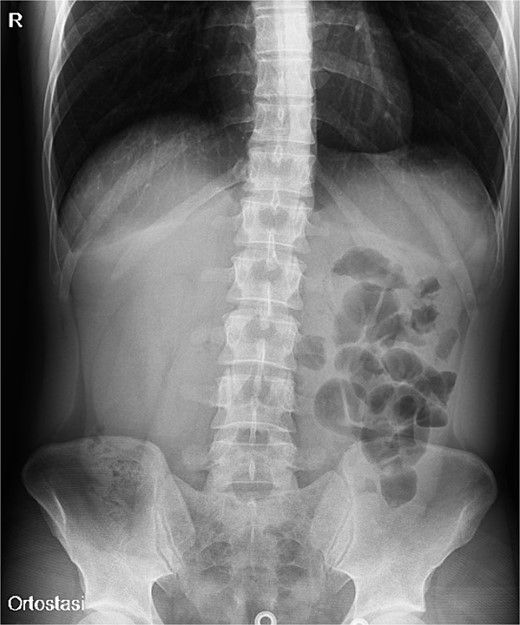

A 31-year-old male was complaining episodes of abdominal pain in the umbilical region with nausea. In medical history he underwent an appendectomy. Chronic gastritis was found on esophagogastroduodenoscopy (EGD) and proton-pump inhibitors (PPI) treatment was started, with regression of symptoms. After two months, he took ketoprofen for back pain for two days when a severe abdominal pain in the umbilical and right iliac region started, with nausea and vomit. He had normal vital signs and tenderness in the right lumbar and iliac regions. Blood exams showed leucocytosis (GB 14.120 × 106/ml) with neutrophilia (88%). A plain abdomen X-ray showed absence of representation in the right regions, with small bowel loops’ distension on the left (Fig. 1). An abdomen US displayed the presence of visceral distension with cockade appearance, consistent with an inflammatory condition of the cecum and the ileocecal site, with wall thickening of 6 up to 10 mm and free fluid near the cecum (Fig. 2). Contrast-enhanced CT confirmed wall thickening of the last ileal loop and the cecum up to 20 mm (Fig. 3A and B). Antibiotic therapy was started. The next day the pain worsened and there was an abdominal mass in the right iliac region with rebound tenderness. Blood examination showed further increase in leucocytosis (GB 18560) and a new CT was done. The wall thickening increased up to 24 mm, and the last ileal loop was more hypointense, with a twisted appearance around its mesentery (Fig. 3C). Exploratory laparotomy was performed. During surgery we found an ileal intussusception of the distal ileum near the cecum, and an ileocecal resection with ileo-colic anastomosis was done. On the first post-operatory day he developed haematochezia and acute anaemia, so he underwent reintervention with resection of the anastomosis and ileostomy. The following post-operative course was uneventful.

Plain abdomen X-ray showing limited visibility of the colon on the right side with small bowel loops’ distension on the left regions, without free air.